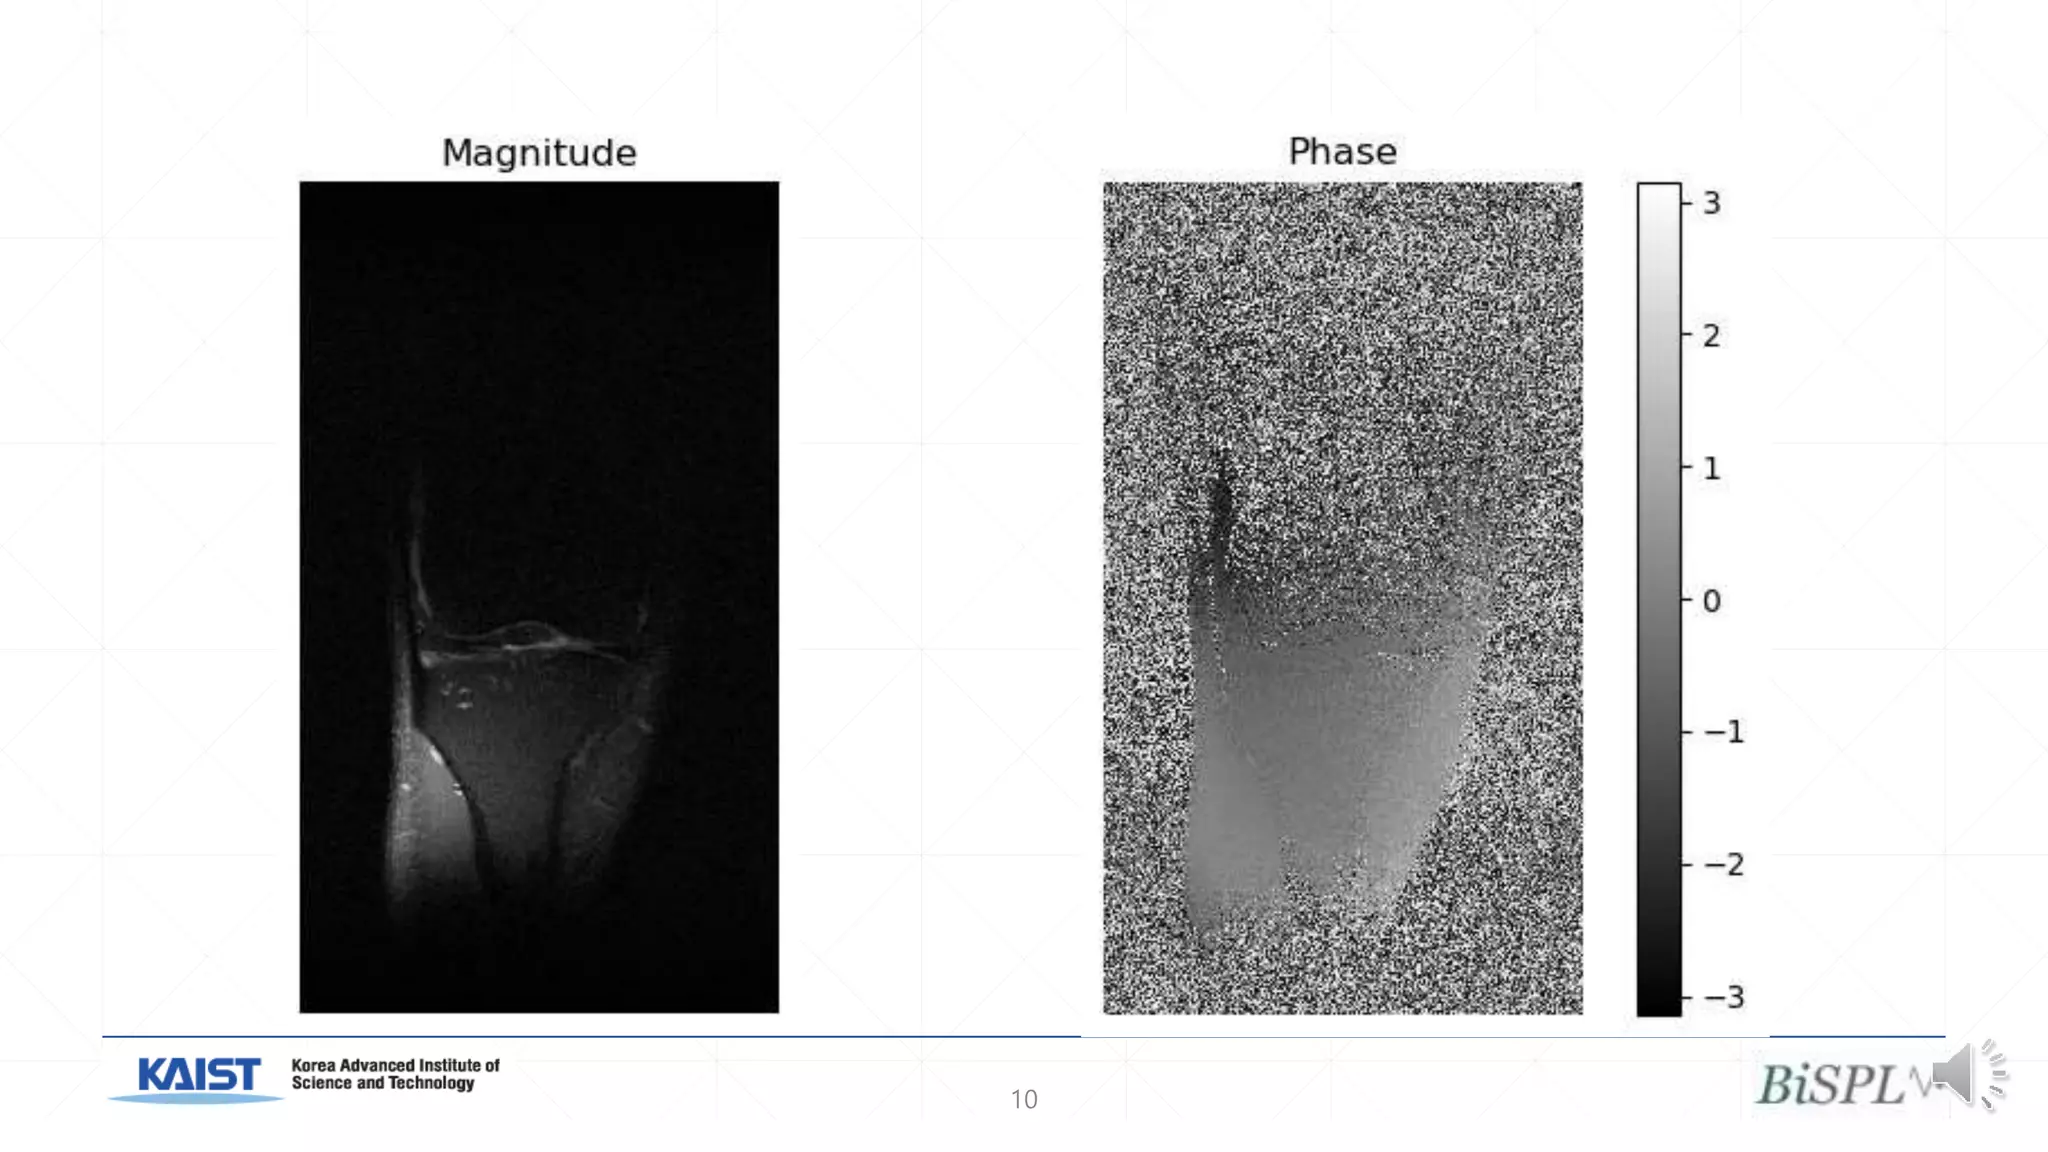

• #11 Image domain learning for MRI loses the phase information of the complex-valued image. The images above show the magnitude and phase from a single coil in a slice in an MRI scan. While this means that the images cannot be converted back into k-space, for k-space input consistency, we find that the magnitude images contain enough information to allow high quality reconstruction.

• #10 Image domain reconstruction is the form used by the vast majority of deep learning image reconstruction models. Over the last few years, through extensive experimentation, it has been proven to work on a wide array of images. While this discards the complex-image phase information, this solved the problem of handling complex numbers.